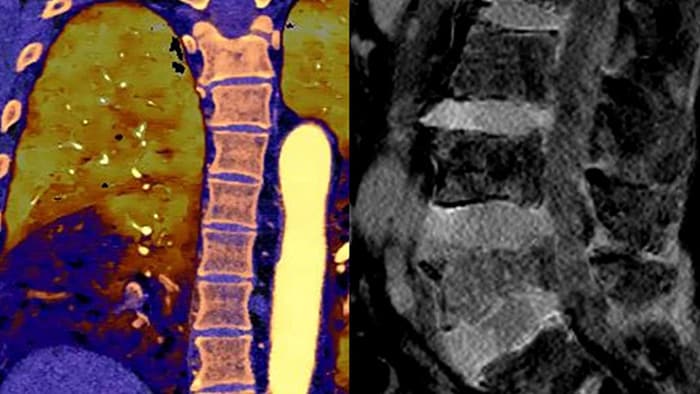

Vá além da CT convencional. Veja de que forma os vários tipos de resultados obtidos com deteção espectral podem aumentar a fiabilidade do seu diagnóstico.

A nossa CT com detetor espectral da Philips permite obter dados convencionais e espectrais numa única aquisição, sem qualquer alteração do nosso atual fluxo de trabalho.